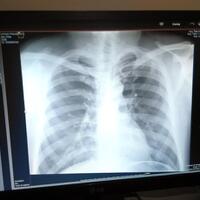

Ini masalahnya foto bagian bawahnya mungkin gak kebaca, soalnya Ane gak bisa liat batas paru-paru dengan diafragma Ente, gunanya utk mengetahui sudut di masing-masing pojok kanan dan kiri agar dipastikan pleuritis tidaknya. Kalo lambung Ente ada masalah gak, kaya maag gitu? kalo masalah magh si

Ada batuk juga gak Gan? Trus yg dominan sakitnya dada kiri apa kanan? Pernah gak ngerasain sakit di bawah tulang rusuk Ente? Dari bacaan rontgen paru kanan terkesan lebih putih, yg bisa jadi ada proses peradangan di situ, bisa berupa pleuritis (radang selaput paru). Di paru kiri yg bintil putih di

selamat pagi dok.. saya mau nanya ni seputar paru paru / dada atas tiap pagi setelah bangun tidur pasti di dada atas berasa nyeri, terus kemudian kalo tarif napas dalam dalam juga rasanya nyeri.. ane ga pernah merokok, cuman kehidupanya dikelilingi sama orang perokok, apa itu ngaruh ya ?? trus sa